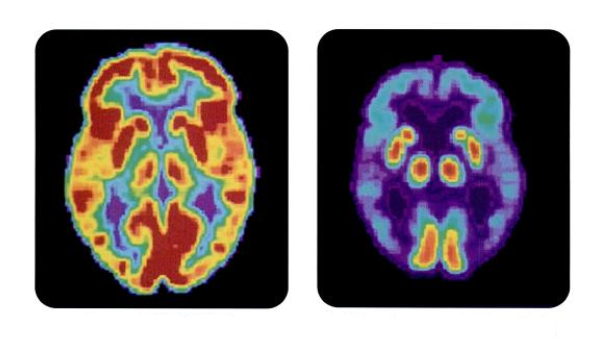

V možganih oseb z Alzheimerjevo boleznijo našli bakterijo

Mednarodna raziskovalna skupina je v možganskem tkivu oseb, obolelih za Alzheimerjevo boleznijo, odkrila prisotnost bakterije Porphyromonas gingivalis. Omenjena bakterija se sicer pretežno nahaja v človeških ustih, kjer lahko povzroča kronično vnetje dlesni oziroma parodontozo. Raziskovalke in raziskovalci so našli dokaze, da bakterija v možganih povzroča razvoj Alzheimerjeve bolezni, osnovali pa so tudi potencialno zdravilo, ki uspešno zdravi okužbo z omenjeno bakterijo v mišjih možganih.

Znanstvenice in znanstveniki so potrdili sum, da se omenjena bakterija nahaja v možganskem tkivu oseb, ki so imele Alzheimerjevo bolezen. Glavni simptomi te napredujoče možganske motnje so težave pri spominu in mišljenju. Eden od vzrokov za nastanek bolezni je tvorba nevrofibrilarnih pentelj. Glavna komponenta nevrofibrilarnih pentelj je protein tau, sestavni del struktur, ki živčnim celicam dajejo obliko in posledično sposobnost delovanja. Pri obolelih pa se zaradi tvorbe nevrofibrilarnih pentelj strukture možganskih celic podrejo.

S primerjavo možganskega tkiva obolelih in zdravih oseb so znanstvenice in znanstveniki pri obolelih opazili genetski material bakterije Porphyromonas gingivalis. Odkritje kaže na prisotnost bakterije v možganih oseb z Alzheimerjevo boleznijo.

Raziskavo so nadaljevali s preučevanjem encimov, ki jih bakterija izloča. To so proteaze, ki imajo sposobnost razgradnje proteinov. Med drugimi lahko razgradijo tudi že omenjene proteine tau, ki so pomembni za ohranjanje strukture živčnih celic. V raziskavi so s pomočjo analitskih tehnik zaznali produkte razgradnje proteina tau. Ugotovili so, da ga razgradijo proteaze, ki jih izločajo bakterije Porphyromonas gingivalis. Te s svojim delovanjem torej škodljivo vplivajo na strukturo živčnih celic in posledično oslabijo njihovo delovanje.

V raziskavi so odkrili enega izmed verjetnih vzrokov za nastanek Alzheimerjeve bolezni. Našli so namreč pomembno povezavo med pojavom bakterije Porphyromonas gingivalis v možganih ter boleznijo. Glede na lastnosti encima, ki ga bakterija izloča, jim je obenem uspelo ustvariti molekulo s terapevtskim učinkom, ki bo v prihodnosti morda igralo vlogo pri zdravljenju opisane duševne motnje.